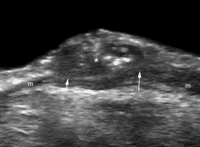

Furthermore, other selection forces not related to perfusion are likely to be present within tumors. For example, evolutionary models suggest that cancer cells, even in stable microenvironments, tend to speciate into “engineers” that maximize tumor cell growth by promoting angiogenesis and “pioneers” that proliferate by invading normal issue and co-opting the blood supply. These invasive tumor phenotypes can exist only at the tumor edge, where movement into a normal tissue microenvironment can be rewarded by increased proliferation. This evolutionary dynamic may contribute to distinct differences between the tumor edges and the tumor cores, which frequently can be seen at analysis of cross-sectional images (Fig 5).

Figure 5a: CT images obtained with conventional entropy filtering in two patients with non–small cell lung cancer with no apparent textural differences show similar entropy values across all sections.

Figure 5b: Contour plots obtained after the CT scans were convolved with the entropy filter. Further subdividing each section in the tumor stack into tumor edge and core regions (dotted black contour) reveals varying textural behavior across sections. Two distinct patterns have emerged, and preliminary analysis shows that the change of mean entropy value between core and edge regions correlates negatively with survival.